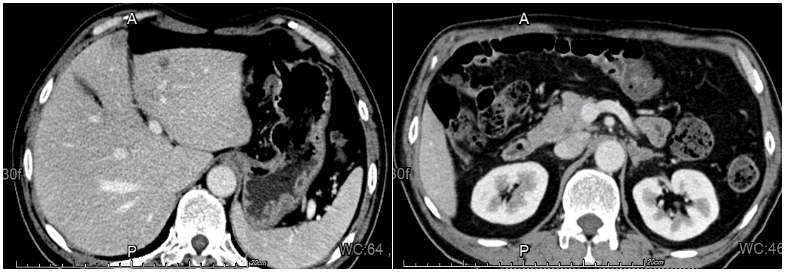

全腹部增强CT(2022-05-30):1、左侧肾上腺结节,较大者直径约1.3cm,增强呈不均匀强化,结合病史,不除外转移瘤可能。2、肝脏左叶低密度影,增强边缘可疑强化,转移?

图2.全腹增强CT

二线治疗第1周期后复查增强CT(2022-07-25):与2022-06-29CT对比:1.左肺上下叶肿瘤性病变(较大截面大小约5.9cm×4.5cm)伴阻塞性炎症,病灶较前缩小;肿块旁多发小结节,考虑转移灶,较前缩小;左肺门及纵隔多发转移瘤,较前缩小。2.右肺上叶及双肺下叶点状影,左肺下叶点状钙化灶。与2022-05-30CT对比:1.左侧肾上腺结节(较大者直径约1.0cm)考虑转移,病灶较前缩小。2.原片所示肝内转移灶本次检查显示欠清晰。

二线治疗第3周期后复查增强CT(2022-09-25):与2022-07-25CT对比:左肺上下叶肿瘤性病变伴阻塞性炎症(较大截面大小约5.1cm×3.2cm),肿块较前大致相仿,周围炎症较前略有吸收、减少;左肺门及纵隔多发淋巴结转移,部分较前略显缩小。与2022-07-25CT对比:1.左侧肾上腺肿块(最大横截面约3.4×2.1cm),较前增大,考虑肾上腺转移。2.肝右叶小囊肿可能。

二线治疗第3周期后疗效评估结果:肺部及纵隔淋巴结病灶为PR;肝脏病灶为CR;左肾上腺病灶为PD;总体疗效评价为PR。

该例患者为小细胞癌与鳞癌复合型C-SCLC,初诊伴左肾上腺转移、肝转移,预后差,治疗选择少。该患者一线使用斯鲁利单抗联合依托泊苷+卡铂化疗方案进行治疗1周期后,影像学显示肺部病灶退缩不明显。考虑患者合并鳞癌成分,可能对于EC方案不敏感,因此换用二线治疗方案。经1周期斯鲁利单抗联合白蛋白紫杉醇+卡铂治疗后,患者咳嗽、咳痰症状好转,肿瘤NSE标志物明显下降,影像学提示肺部病灶出现明显退缩,且肝脏转移瘤及左侧肾上腺病灶均较前缩小,疗效达PR。患者使用斯鲁利单抗联合白蛋白紫杉醇+卡铂方案治疗3周期后,影像学检查提示肺部及纵隔淋巴结病灶疗效持续PR,肝脏病灶疗效达CR,仅左肾上腺病灶有PD征象。目前患者正在接受局部放疗,以期进一步提高肿瘤局部控制率。患者治疗期间未出现不可控irAE,安全性好。